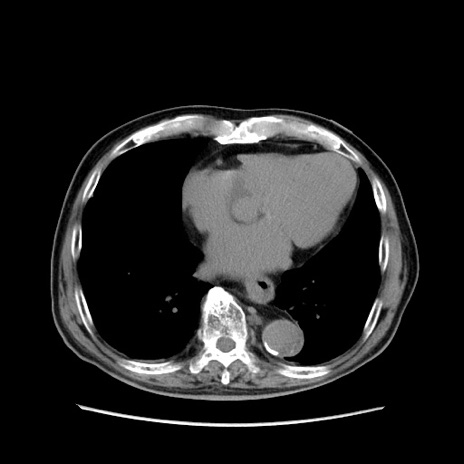

症例24(横断像)

【症例】80歳代男性

【主訴】左側腹部痛、嘔吐

【現病歴】本日早朝より左腹部に痛みあり。昼頃嘔吐認めたため、救急要請。

【既往歴】直腸癌(Mile手術)、胆摘

【身体所見】意識清明、BT 35.9℃、BP 221/93mmHg、SpO2 97%(RA) 、腹部:左ストーマ周囲に限局性の腹部膨隆あり。 膨隆部自発痛・圧痛あり・軟。

【データ】WBC 7700、CRP 0.09